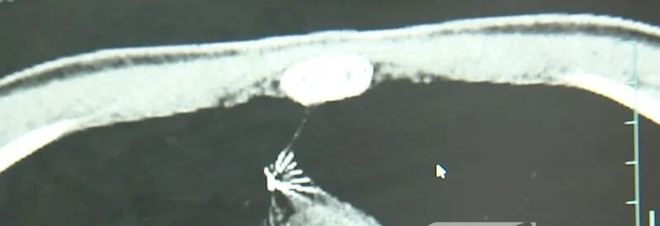

近日,安徽17岁小伙小陆参加征兵体检,胸片结果显示:胸腔内有一处金属高密度影,形态细长,像一根针。进一步的CT检查确认,异物是一枚金属针,斜插在肺组织内,位置十分凶险。

异物取出后,发现针长5cm左右

近日,医院为小陆实施了mini单孔胸腔镜微创手术,切口仅2cm左右,成功将针完整取出。取出后发现,这根针长达5cm左右。